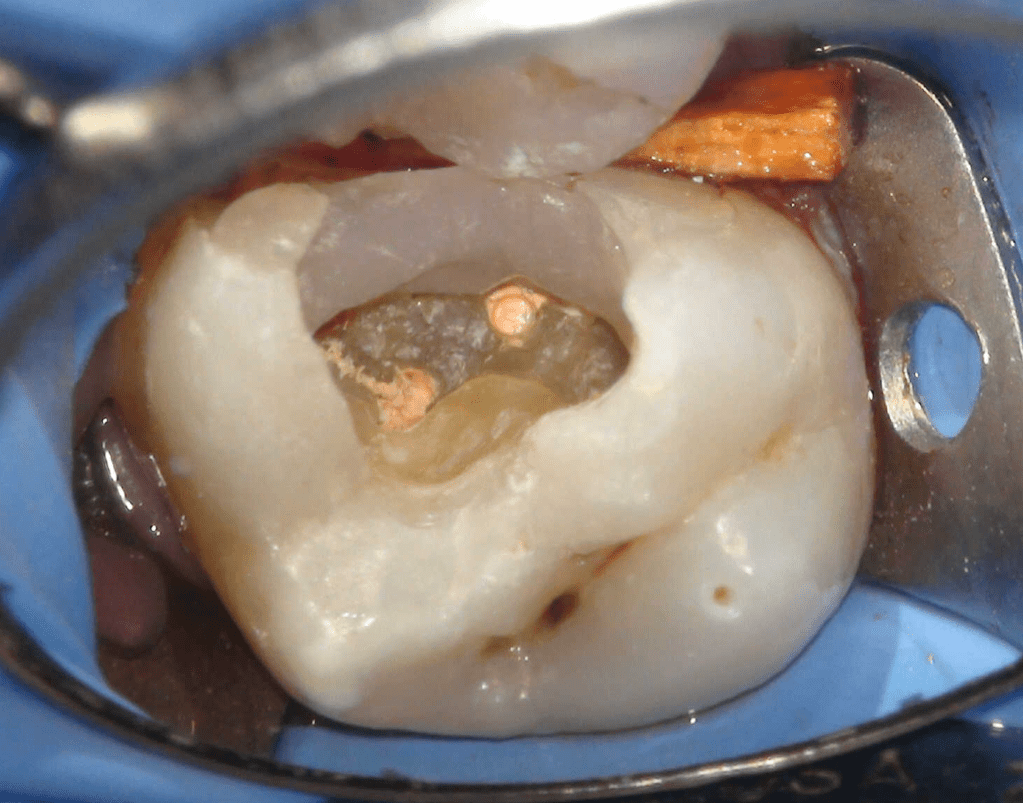

Pulpotomía biodentine + reco preendio